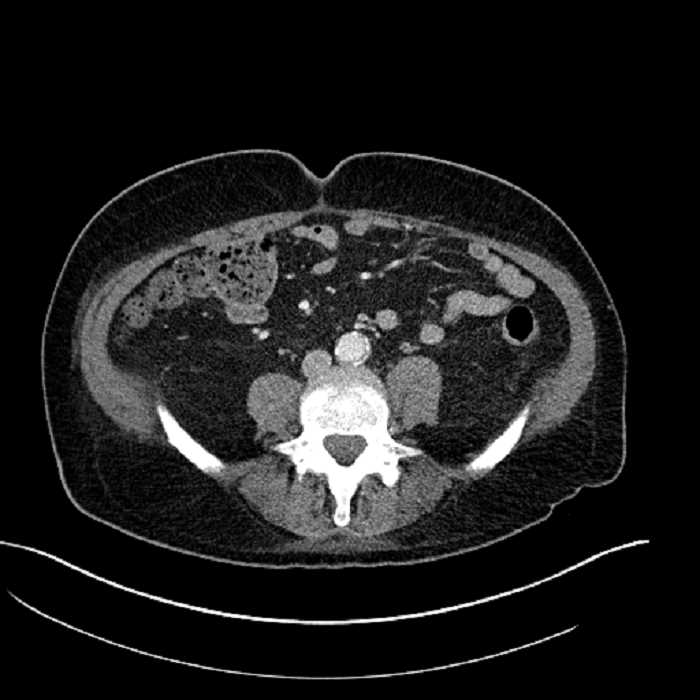

Age: 63

Sex: Male

Indication: Abdominal pain

• Large fluid density structure in hepatic segments 7 and 8 measuring 10 x 7 x 7 cm with internal septation and circumferential ill-defined low density compatible with edema

• Peripherally enhancing subcapsular collections along the anterior margin of the left hepatic lobe measuring 3 x 1 cm and 2 x 1 cm

• Clearly marginated fluid density structure in segment 7 and several other scattered tiny hypodensities, which likely represent cysts

• Mild mural thickening of a segment of the sigmoid colon with adjacent fat stranding and a 1.5 cm fluid and gas collection along the tip of an inflamed diverticulum

• Loss of the normal fat plane between this collection and adjacent loops of small bowel, which demonstrate mural thickening

Acute sigmoid diverticulitis complicated by a small contained perforation and a large abscess in the right hepatic lobe. Additional small subcapsular abscesses along the anterior margin of the left hepatic lobe.

Additionally, loss of the normal fat plane between the peridiverticular collection and adjacent thickened loops of small bowel raises the potential for an enterocolonic fistula.

• The classic CT imaging appearance is a double target sign with internal low density surrounded by an internal enhancing rim (capsule) and a low density external rim (edema)

Hepatic abscess showing the double target sign with low density internally surrounded by a thin inner enhancing rim (red arrow) and ill-defined outer low density rim (yellow arrow). Blue arrow indicates an internal septation. Red arrows: additional smaller subcapsular abscesses. Red arrow: focal contained perforation associated with diverticulitis.